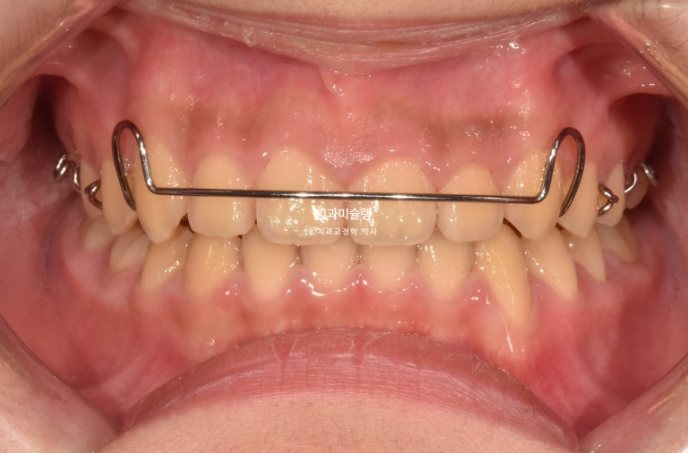

치료결과가 성인교정치료 결과에 준하는 만큼 유지장치도 성인과 동일하게 들어갑니다.

단 과개교합 재발 방지를 위해서 유지장치에 ABP교합판을 추가하는 것이 안전합니다.

과개교합만 재발이 안된다면 이 친구는 성인이 되어 다시 교정을 안해도 될거에요